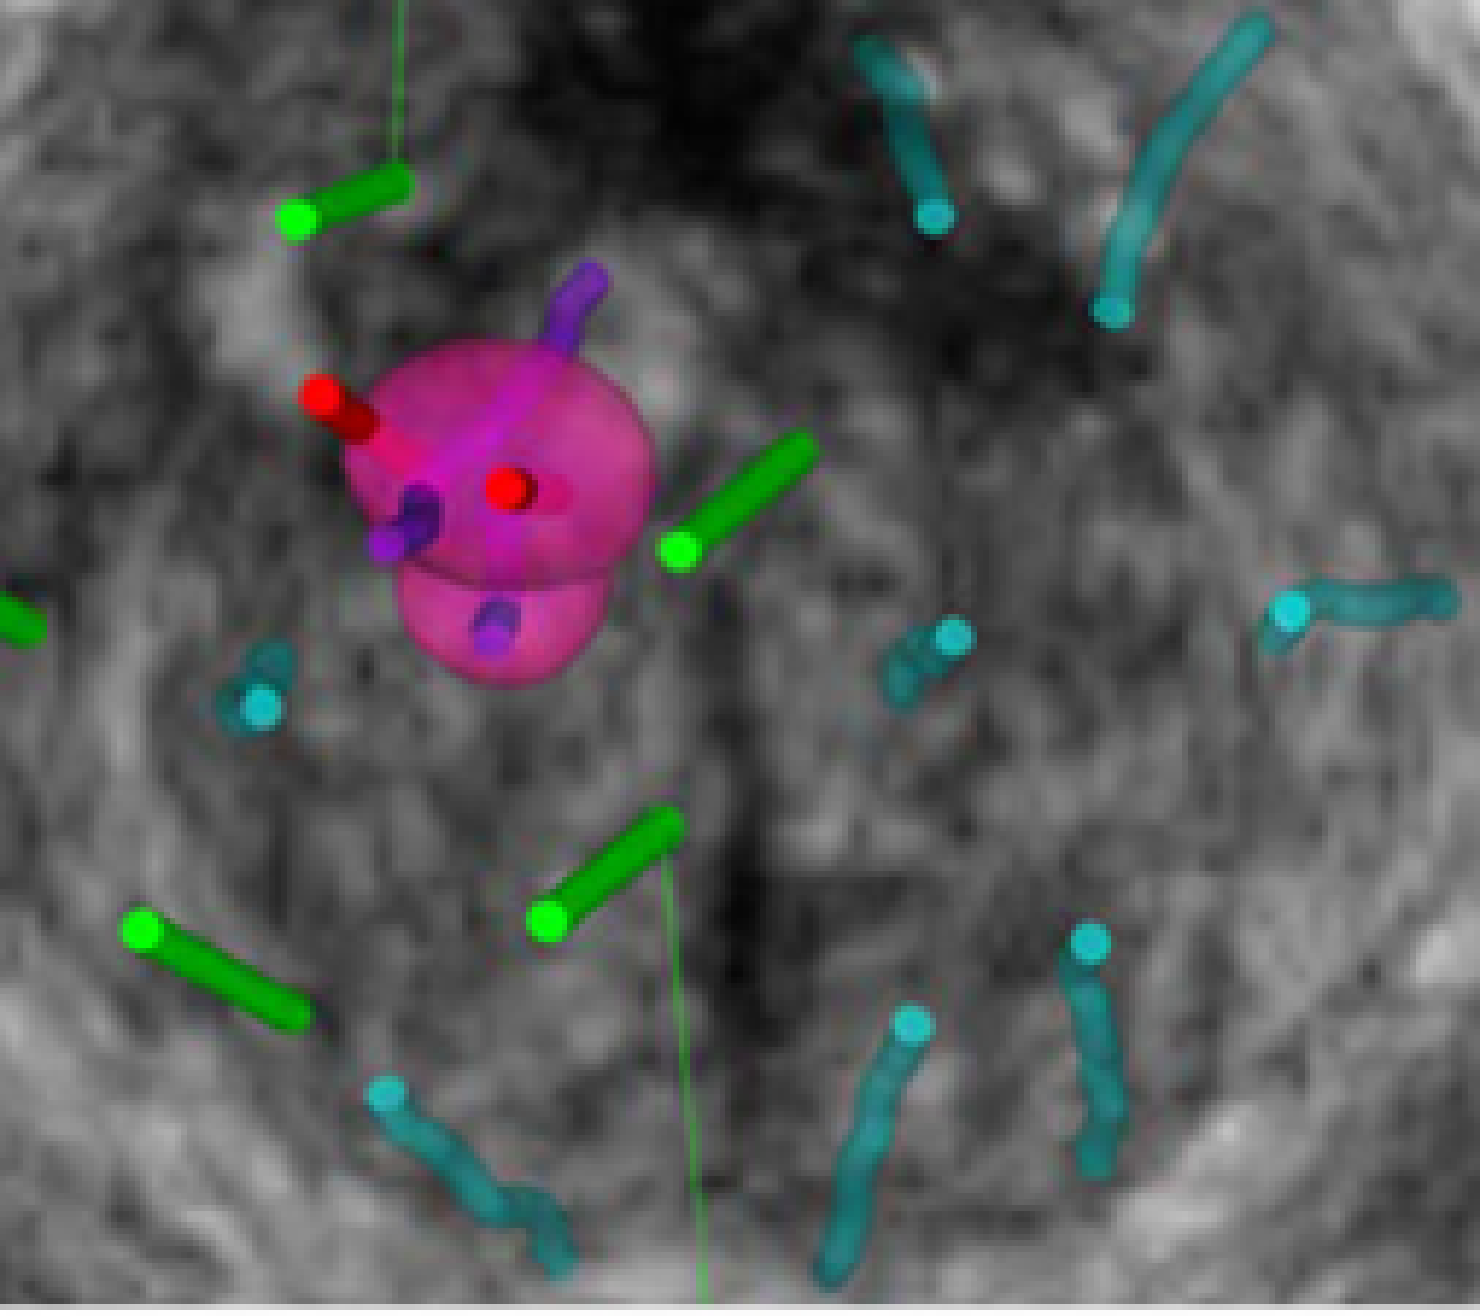

Μοναδικά εξοπλισμένο σύστημα με τρισδιάστατες ηχοβόλες κεφαλές υπερήχων και την κατοχυρωμένη με δίπλωμα ευρεσιτεχνίας τεχνολογία της KOELIS®, Organ-Based Tracking Fusion® το KOELIS Trinity® προσφέρει μέγιστη ακρίβεια και σιγουριά στην οριοθέτηση και τη στόχευση βλαβών του προστάτη.

Οι ύποπτες βλάβες ορίζονται εύκολα και οριοθετούνται στο KOELIS Trinity® ή σε ειδικό λογισμικό. Μόλις ολοκληρωθεί η μαγνητική τομογραφία θα συγχωνευτεί με τρισδιάστατη εικόνα υπερήχων χάρη στην ελαστική σύντηξη.

Η τεχνολογία OBT Fusion® επιτρέπει την οπτικοποίηση της θέσης του πυρήνα της βλάβης πριν από τη δειγματοληψία καθώς και την ακριβή καταγραφή της θέσης του πυρήνα μετά τη δειγματοληψία.

Όλες οι πληροφορίες καταγράφονται σε έναν 3D χάρτη για τον ασθενή, έτοιμο να συμπληρωθεί με αποτελέσματα ιστοπαθολογίας και MRI μετά την επέμβαση.